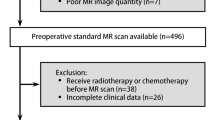

Two reviewers conducted the search, selected the studies, and extracted data from each study independently. From a total of 30 papers, 10 research articles on predicting lymph node metastasis in breast cancer using a radiomic approach in breast MRI were considered eligible.

Our search found 30 publications on predicting axillary lymph node status in BC patients. All these studies were published from 2017 to 2020. Ten studies were retrospective in design (Chai et al. 2019; Liu et al. 2019a, b; Cui et al. 2019; Dong et al. 2018; Han et al. 2019; Tan et al. 2020; Shan et al. 2020; Yu et al. 2020); only Liu et al. (2020) was prospective.

Some bias were described by the authors in the discussion paragraphs. In most cases, the small samples size and the monocentricity were considered the major limitations. The population investigated was composed by less than 200 patients for seven studies (Chai et al. 2019; Liu et al. 2019a, b, 2020; Cui et al. 2019; Dong et al. 2018; Shan et al. 2020). Yu et al. used the largest sample size (over 1000 patients) to develop and validate DCE-MRI radiomic signatures for preoperative identification of ALNM. Eight studies lacked external validation for their models (Shan et al. 2020; Yu et al. 2020).

This review has some important weaknesses. The first is the low number of articles analyzing lymph node status in breast cancer, with all studies but one being retrospective in design. The population numbers are quite low for most studies, although this is in accordance with their experimental nature. However, we expect that, as the application of radiomics progresses and becomes more widespread, there will be an increase in the number of cases examined, also considering the possibility of dataset sharing.